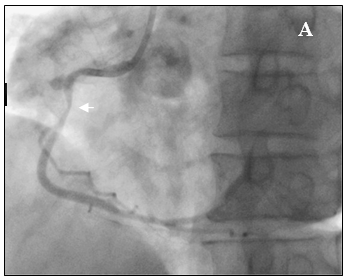

Bệnh nhân được chẩn đoán nhồi máu cơ tim cấp vùng hoành giờ thứ 2, Block A-V độ 3, có chỉ định chụp mạch vành cấp cứu. Bệnh nhân được kích nhịp bằng Atropin, Dopamin và truyền dịch chống choáng trên đường chuyển đến phòng thông tim. Kết quả chụp mạch vành cho thấy hẹp 90% ở đoạn xa RCAI (hình 6a), tuy nhiên khi chuyển sang góc chụp kế tiếp chúng tôi phát hiện thêm một chổ hẹp thứ hai rất nặng ở đoạn gần RCAI tại vị trí sát ngay đầu ống thông can thiệp (hình 6b). Nghi ngờ tổn thương do co thắt nên chúng tôi bơm 200µg Nitroglycerin vào RCA và chụp lại sau 2 phút. Kết quả chổ hẹp nặng ngay sát đầu ống thông can thiệp đã hoàn toàn biến mất (hình 7b), chổ hẹp đầu tiên ở đoạn xa RCAI chỉ còn 30% (hình 7a). Như vậy, nhồi máu cơ tim vùng hoành là do co thắt RCA tại vị trí mãng xơ vữa.

Hình 6: Tổn thương hẹp nặng RCAI nghi do co thắt mạch vành

Hình 7: (A) Hẹp 30% đoạn xa RCAI

(B) Không còn chỗ hẹp gần đầu Guiding